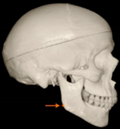

Three points determined the Acta plane: O, F right (FR), and F left (FL) (Table 2). Point O is the midpoint between the most craniodorsal point of the dorsum Sella and the most posterior dorsal point of the Basion in the midsagittal plane (Figure 1). Both points F are a result of the intersection between two lines: the line that connects the most inferior points of the lower orbital margins, right and left, and a line perpendicular to this line that runs through the most external points of the orbital margins, right and left (Figure 2). The new transverse reference plane, the Acta plane (Figure 2), is created by connecting the O-point (Figure 1) with FR and FL (Figure 2).

Figure 2.

(A) Construction of the F-points (right and left), frontal view. The F-points are originated from the intersection between the line connecting points A (the most inferior point of the lower orbit) and the perpendicular line to it that passes through points B (most external/lateral point of the Orbita). (B) Transverse view of the ACTA plane.